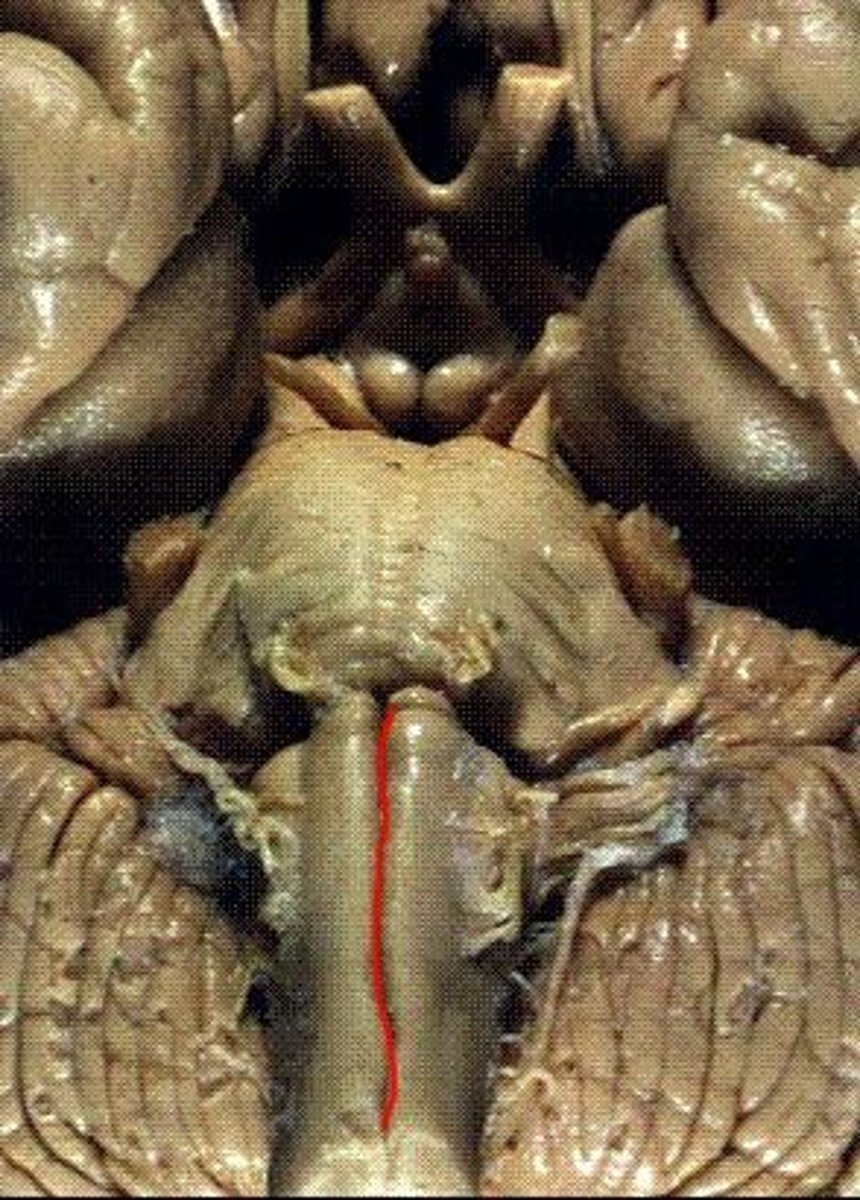

two ridges of tissue on the ventral aspect of the medulla, separated from each other by the ventral median fissure

pyramids

area where most corticospinal fibers decussate over the lower medulla, therefore obscuring the ventral median fissure

pyramidal decussation

elongated mounds of tissue lateral to the medullary pyramids

olives

vertical groove dorsolateral to the inferior olive on each side that gives rise to CN IX and X

postolivary sulcus

white matter stalks that connect the medulla to the cerebellum

**these help to form the lateral walls of the caudal portion of the 4th ventricle

inferior cerebellar peduncles

medial paired ridges of tissue on the dorsal aspect of the closed portion of the medulla

tractus gracilis

lateral paired ridges of tissue on the dorsal aspect of the closed portion of the medulla

tractus cuneatus

superior ends of the medial paired ridges of tissue on the dorsal aspect of the closed portion of the medulla, formed by namesake nuclei

gracilis tubercles

superior ends of the lateral paired ridges of tissue on the dorsal aspect of the closed portion of the medulla, formed by namesake nuclei

cuneatus tubercles

V-shaped boundary of the caudal aspect of the 4th ventricle that marks the boundary between the open and closed portions of the medulla

obex